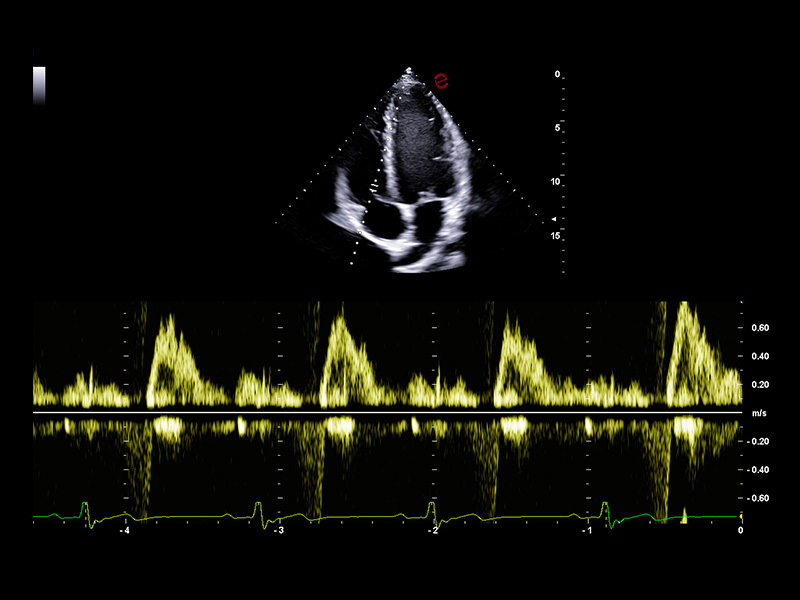

AI-based cardiac measurements for speed and consistency

Esaote’s AutoEF and AutoCM tools are designed to bring a step ahead in the device use experience. With advanced AI algorithms, AutoEF automatically recognizes apical views and traces endocardial borders offering a proposal of left ventricular volumes and ejection fraction in just seconds. AutoCM complements this by automatically suggesting ventricular wall thickness, internal diameters, and derived values such as LV mass and fractional shortening directly from parasternal views. Moreover, AutoCM assists cardiologists by automatically recommending a calculation of the E/A wave ratio of the mitral valve, providing crucial information on diastolic function.

Together, these tools help clinicians to obtain accurate, guideline-aligned measurements in a fast way, enhancing diagnostic reliability. AutoEF and AutoCM automate key functional and structural measurements—such as ejection fraction, LV volumes, wall thickness, and LV mass— making a smooth workflow, especially in high-throughput clinics.